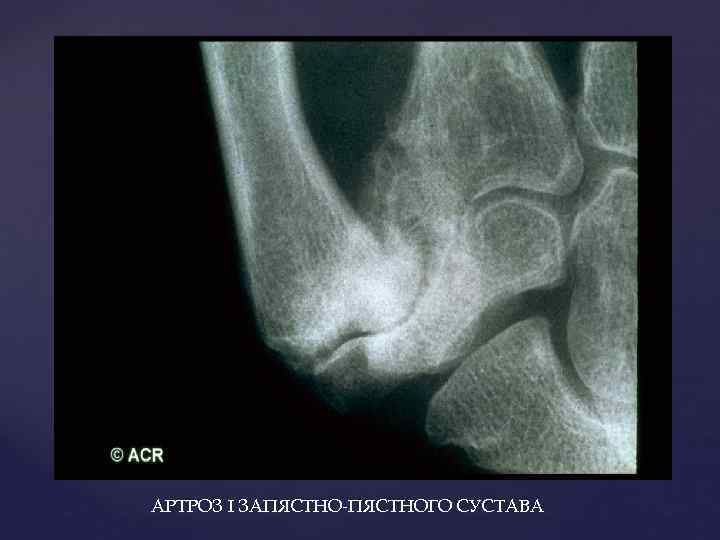

АРТРОЗ I ЗАПЯСТНО-ПЯСТНОГО СУСТАВА

АРТРОЗ I ЗАПЯСТНО-ПЯСТНОГО СУСТАВА